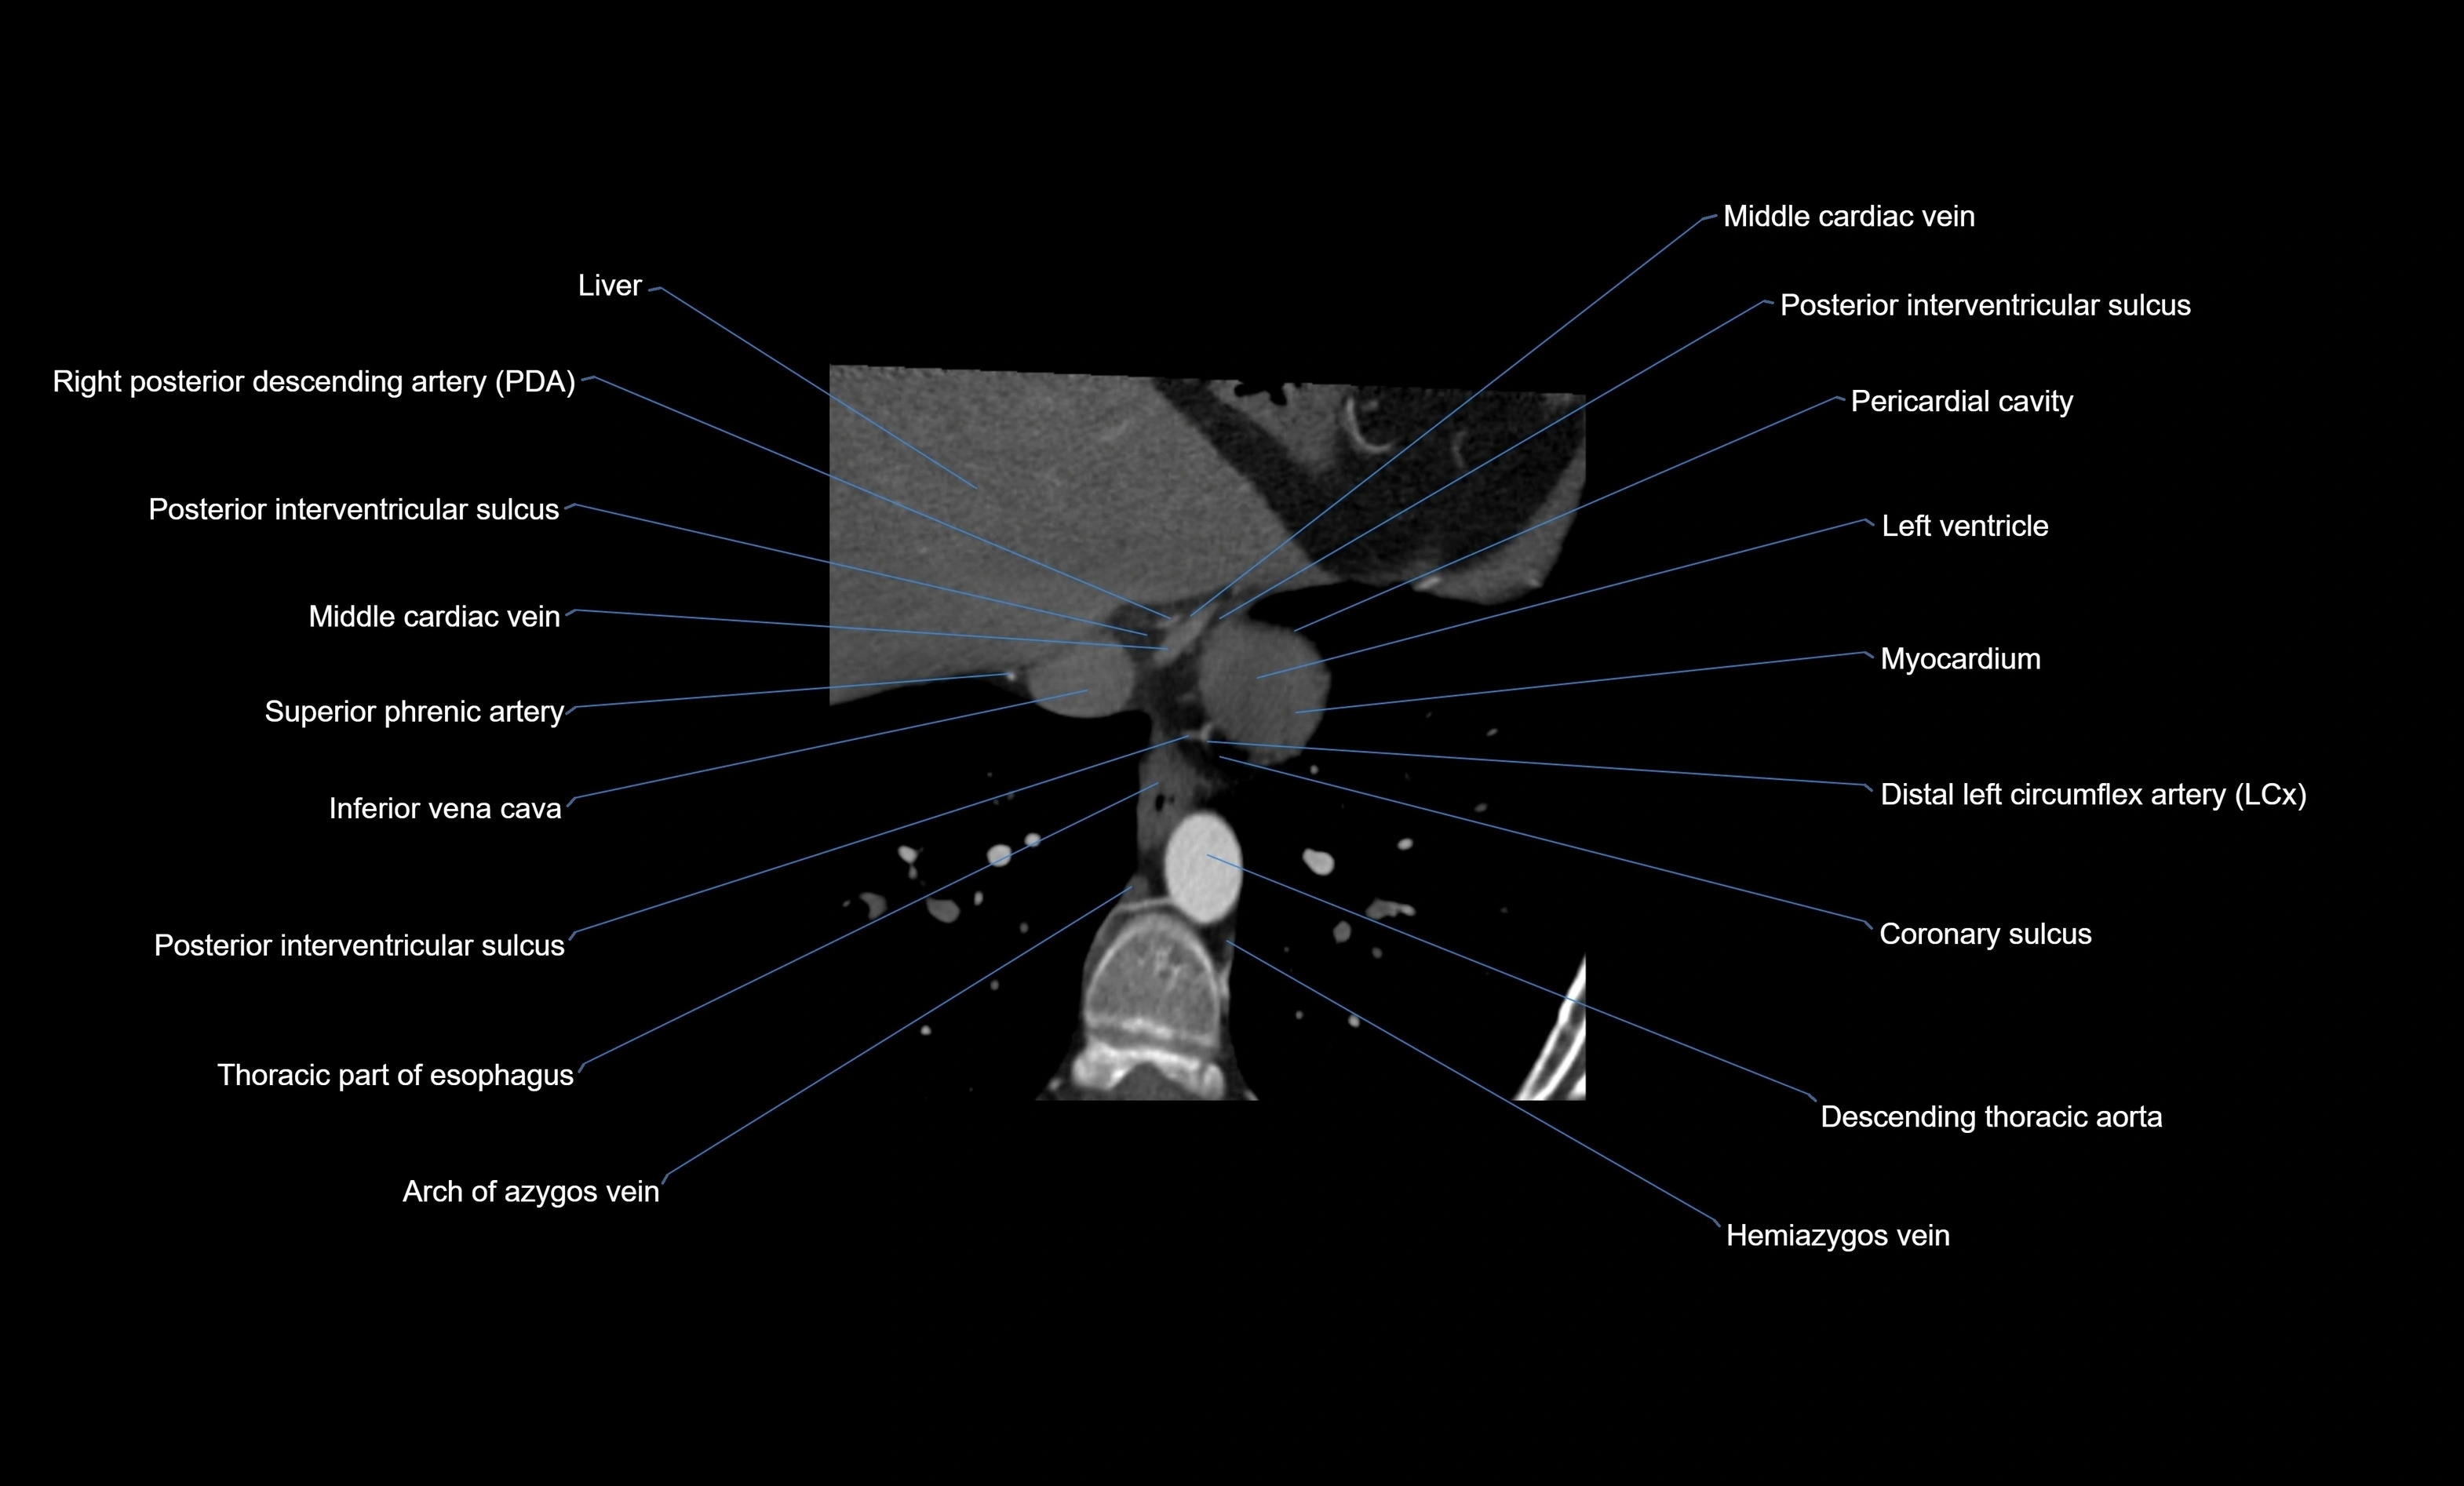

CT images